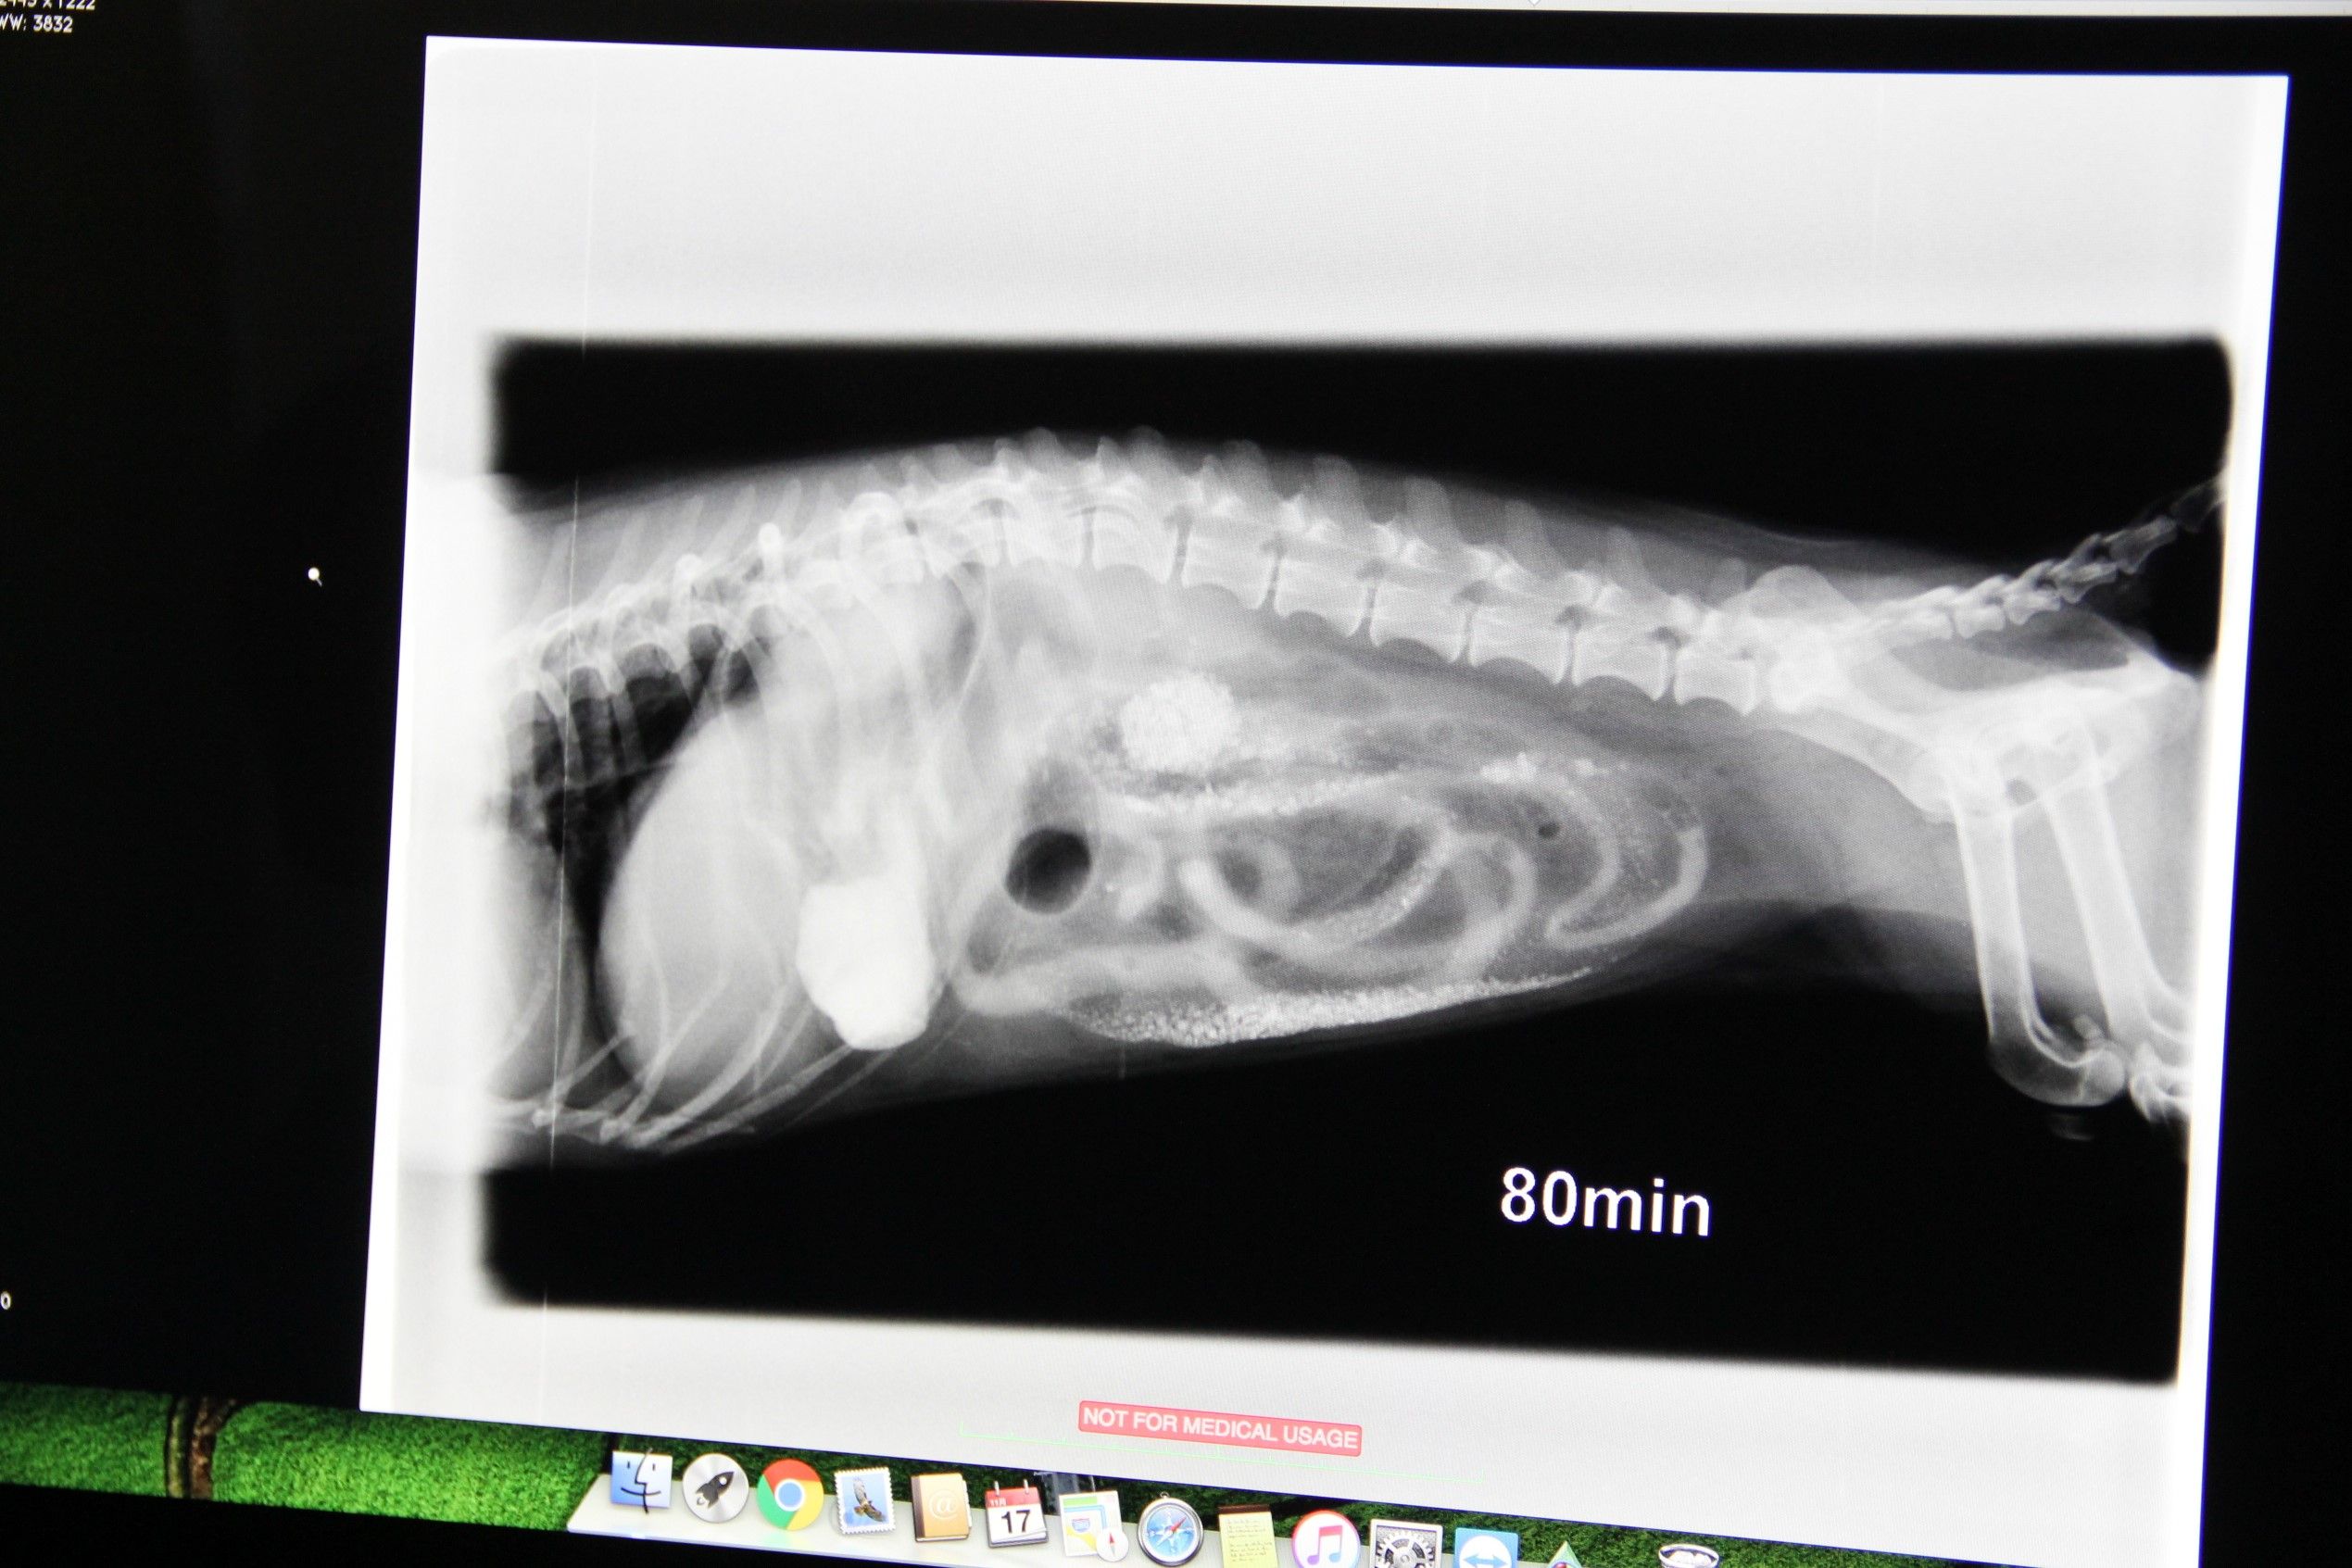

11/16朝の体重:プチ:お休み大地5.0kgメレ4.6kgミント:お休み********************************************************プチ、12歳10ヶ月の開腹手術(異物摘出)の続きです。検査が終わったら電話すると言われたけど心配でとても待っていられない。母や大地メレミントの食事、翌朝の食事の準備等々全て済ませて病院へ。腹水を調べたところ血は混ざっていないので腫瘍ではなく炎症が原因造影検査ですが、造影剤が腸のほうに流れていきません異物に堰き止められているのでしょうこのあとプチは胃に溜まっていた造影剤を全部吐きました造影検査の結果、穴の開いているところはありません砂利とか砂は通常であれば流れていきますが・・・何かの拍子できゅっと詰まってしまったのでしょう回盲部で腸閉塞を起こしている可能性もあります前回(6年前)の異物摘出はどういう手術でしたか? ※胃と腸を切開して摘出、腸壁の薄くなっていたところは縫合腸壁等が薄くなっていなければ切ったところから砂利を指で押し出しますもし破けそうであればもっと切開して摘出することになります白血球が減ってしまっていることで感染症などが非常に怖いので今、増やすために点滴を投与しています準備ができ次第手術に入ります終わったらご連絡しますプチに会えますか?と聞いたら、どうぞ、とのこと・・・怖くて心配でたまらない。でもHITONが暗い顔をしていたらプチが不安になるだけ。『頑張ってね』『また後でね』って撫でながら声をかけて、先生にプチをお願いし自宅へ。続きますプチ大地メレミントに応援クリックよろしくお願いします( 別ウィンドウが開ききるまではそのままでお願いしますm(_ _)m )Instagram登録してみました~プチだいメレミンすたぐらむ 画像をクリックすると移動します今までのハンドメイド作品をまとめました 画像をクリックすると今までの作品をご覧いただけます*******************************************************

11/15朝の体重:お休み********************************************************先日のほったらかしのキャンプ中、プチが下痢と嘔吐。すぐキャンプ場近くの病院に行き診てもらったところ、胃腸炎の診断。でも処方された薬を飲ませても変わらず・・・いつもの自宅近くの病院に電話して状況を説明し、早めにチェックアウトして病院へ。胃腸炎ならお預かりすることもないと思うけれど念のためレントゲンを撮って調べてみましょう撮影後、プチを連れてきてくれて先生が一言やっぱりプチ元気ないかもしれないしばらく待って、再び診察室へ・・・画像を見ながら先生はちょっとびっくりな結果なんですけど腸が砂利でいっぱいですね砂利???キャンプの時か・・・何でそんなものが・・・血液検査の結果、白血球の値が非常に少ないです身体の中で炎症を起こしていると思われます異物で炎症を起こしているところに白血球がみんな出動してしまったのでしょう腹水が溜まっています異物による穿孔を起こし腹膜炎を発症したことが原因か、それとも腫瘍などによるものか1.腹水のチェック 2.血液検査 3.消化管造影(ヨード系)をしましょう※もし腸などに穴が開いていた場合、バリウムが漏れ出すと危ないのでヨード系での検査検査が終わったらお電話しますのでご自宅でお待ちくださいこのままでは弱っていくだけです緊急手術をさせてくださいただ、12歳ということもあり非常にリスクは高いです手術中に心肺停止になる可能性もありますでも手術をお願いするとHITONの心は決まってたので同意書を書き一度帰宅。いつかは訪れる別れの時・・・でも、今じゃない続きますプチ大地メレミントに応援クリックよろしくお願いします( 別ウィンドウが開ききるまではそのままでお願いしますm(_ _)m )Instagram登録してみました~プチだいメレミンすたぐらむ 画像をクリックすると移動します今までのハンドメイド作品をまとめました 画像をクリックすると今までの作品をご覧いただけます*******************************************************